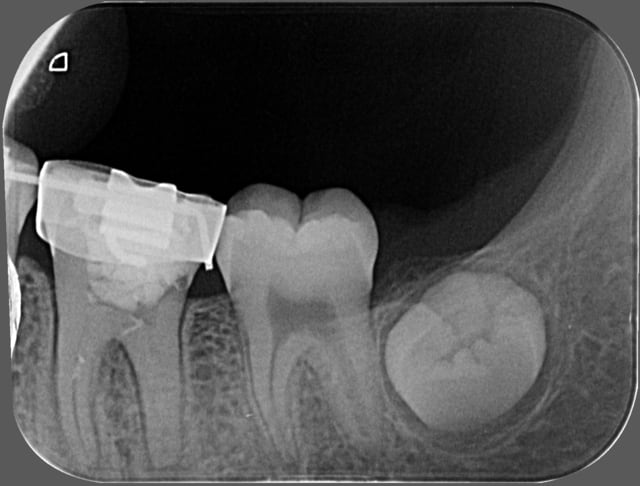

patiente 14 ans 36 cariée pendant le traitement ODF,

Donc dans ce cas là vous me conseillez plutot l'exo ?

Radio prise ce matin, traitement toujours en cours,

Première fois que je vois la patiente